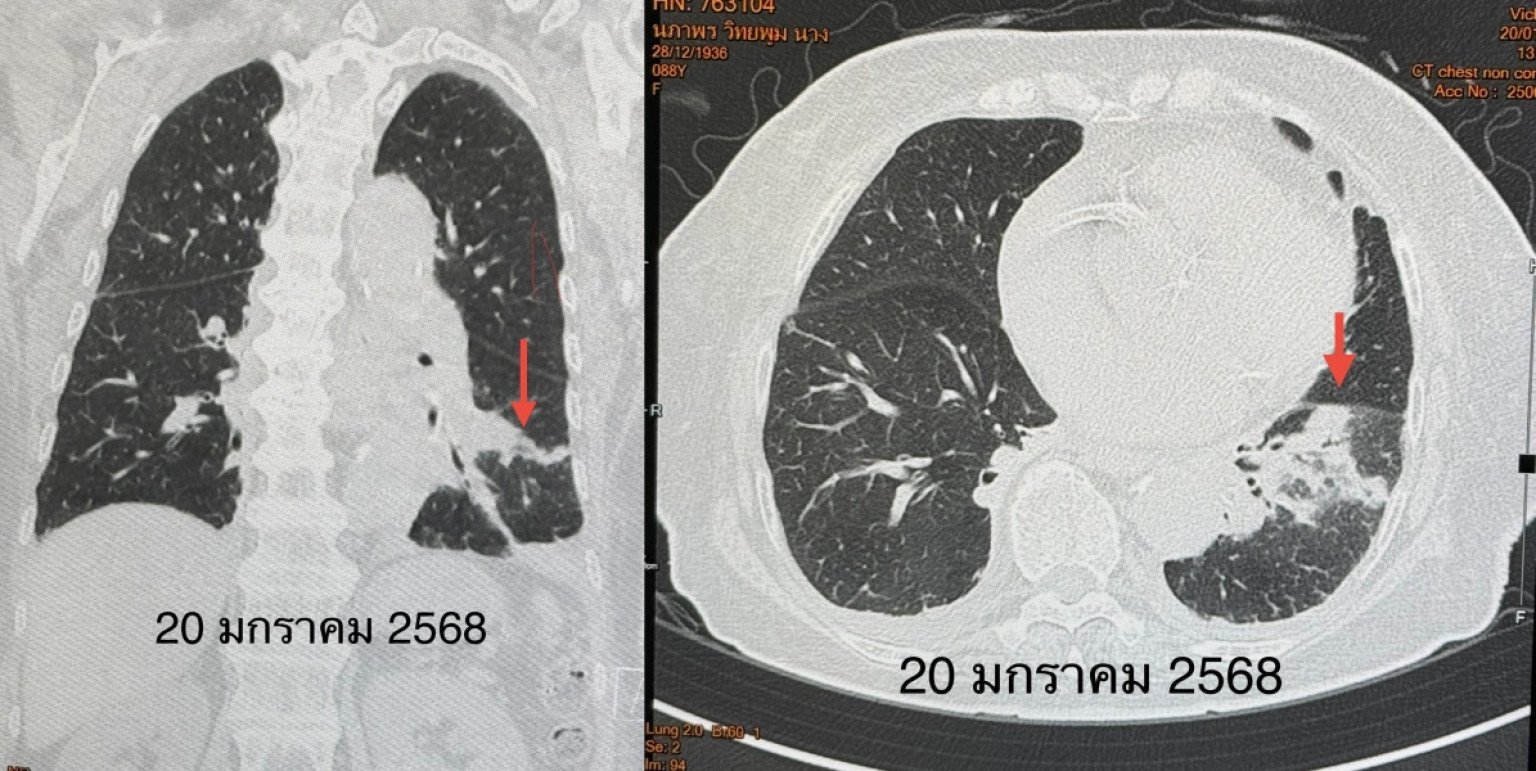

ตรวจร่างกาย ระดับออกซิเจนที่ปลายนิ้วต่ำ 87% ต้องให้ออกซิเจน 2 ลิตร/นาที ไม่มีไข้ ฟังปอดมีเสียงผิดปกติเล็กน้อยที่ปอดข้างซ้ายด้านล่าง เจาะเลือด เม็ดเลือดขาวในเลือดปกติ เอกซเรย์ปอดมีฝ้าขาวในปอดข้างซ้ายด้านล่าง (ดูรูป) ทำคอมพิวเตอร์ปอดยืนยันว่ามีฝ้าในปอดข้างซ้ายด้านล่าง และมีน้ำในช่องเยื่อหุ้มปอดเล็กน้อย (ดูรูป) ตรวจเลือดเม็ดเลือดขาวปกติ แยงจมูกส่งตรวจรหัสพันธุกรรมเชื้อ 22 สายพันธุ์ไม่พบเชื้อ ส่งเลือดตรวจ Legionella pneumophila Antibody IgM positive 1:200